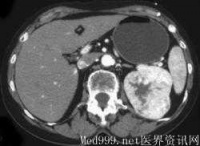

4.CT检查示肾内实质性占位性病变及CT值低的脂肪成份。

cm,病程1个月~7年。主要临床症状为腰部不适、胀痛、包块、出血性休克等。22例均行KUB加IVP和CT检查,2例行MRI检查。IVP表现为正常或提示肾盂肾盏受压变形;B超检查多表现为强回声光团,也表现为混合回声,诊断准确率为86.4%(19/22);CT平扫多表现为圆形或类圆形低密度或极低密度病灶,病灶位于肾实质内或突出于肾轮廓外,诊断准确率为90.9%(20/22)。

的良性肿瘤,由于肾基质缺乏脂肪和平滑肌,故通常认为属错构瘤。有20%肾错构瘤合并节结性硬化症,并双侧同时发生,病变较小,常并发癫痫、智力低下、面部皮脂腺瘤等。肾错构瘤以中年女性为多见。陈承志等报告男女比例为1∶2.25,本组为1∶1.2。 B超结合CT诊断肾错构瘤有重要价值,随着超声、CT和MRI的应用,肾错构瘤的发病率有所增加,术前诊断准确率也有所提高。肾错构瘤与肾细胞癌的影像学鉴别要点在于肾错构瘤含有较多脂肪成分而正常肾及肾细胞癌组织极少或没有,肾错构瘤在B超图像中表现为强回声光团,偶然可见混合性低回声。CT显示比超声图像更敏感,CT值于小-10Hu,因此,典型的肾错构瘤不难诊断。MRI检查时,T1加权像较低,T2加权像又极高。IVU主要了解双肾功能情况,对于评估肾功能不良患者是否进行手术以及手术方式的选择具有重要作用。